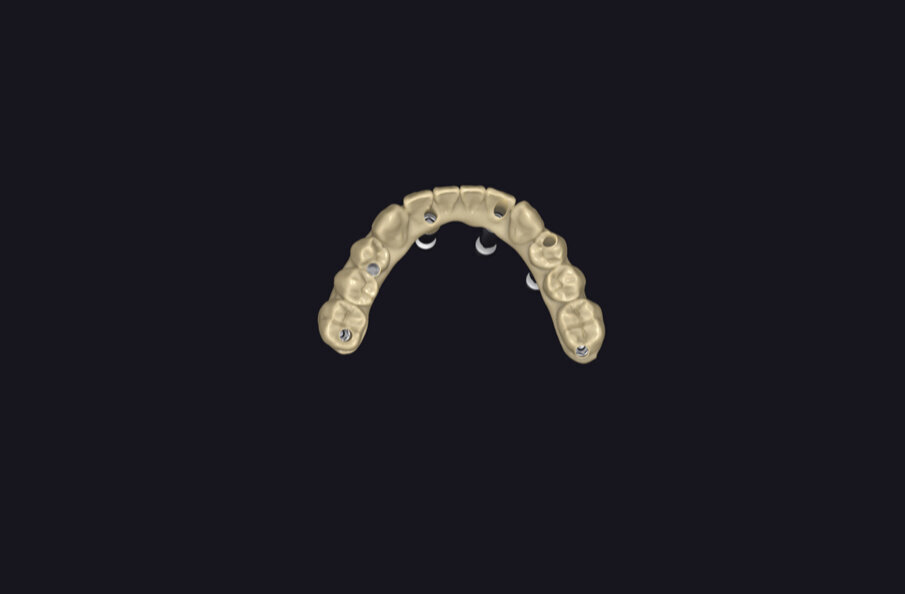

Fig. 12 - Progetto digitale.

Fig. 13 - Flusso digitale.

Fig. 14 - Elaborazione digitale.

Fig. 15 - Fasi di lavoro digitale.

Fig. 16 - Modello digitale e provvisorio.